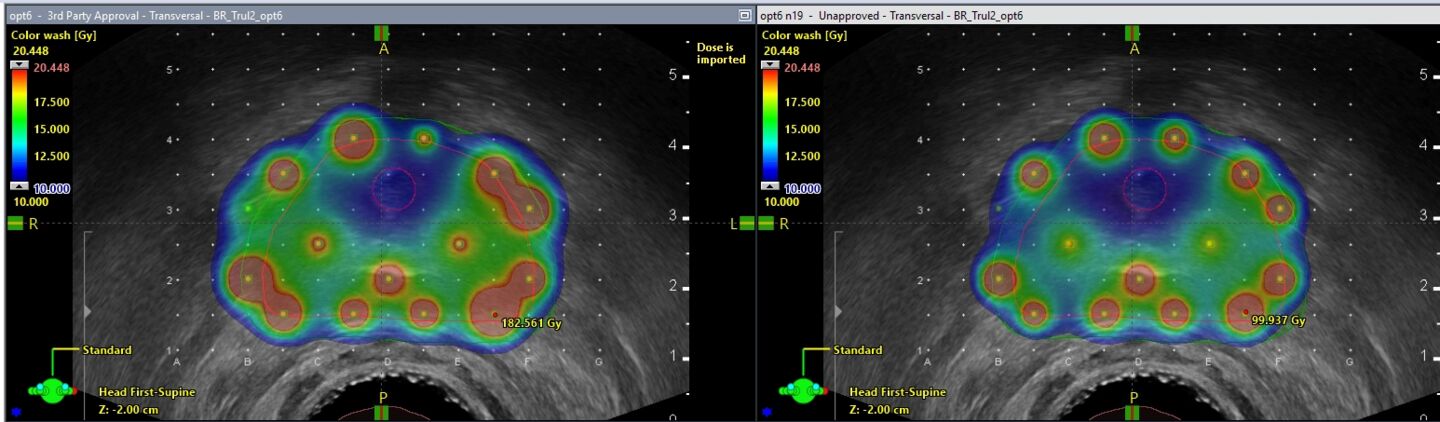

Brachytherapy is a modality of radiation therapy where a small radiation source is placed inside, or close to, a tumour, using hollow needles or applicators. For each treatment, patient specific medical images are obtained with, for example, CT or ultrasound. The aim with the treatment is to irradiate the tumour with a dose that is high enough, while avoiding unnecessary irradiation to nearby healthy organs. The treatment aims are based on the clinical guidelines for each treatment site.

Treatment planning for brachytherapy yields difficult mathematical optimization problems where several contradictory aims need to be considered and prioritised based on the patient-specific anatomy and prerequisites. Furthermore, the planning is commonly conducted while the patient is waiting under some form of anaesthesia, and it is hence important with fast and efficient methods for treatment planning. The treatment planning data contains several uncertainties, for example, where the radiation source is placed and the tumour delineation on the medical images. With methods from robust and stochastic optimization, we investigate how treatment planning can take such uncertainties into account and mitigate them.

In addition to delivery techniques and evaluation criteria which are used in current clinical practice, our research also includes new such methods. Intensity modulated brachytherapy is a new delivery technique using dynamic shields to better shape the dose distribution to the tumour and thus spare nearby healthy organs. For evaluation criteria, artificial intelligence is an important method to model treatment outcomes in treatment planning.